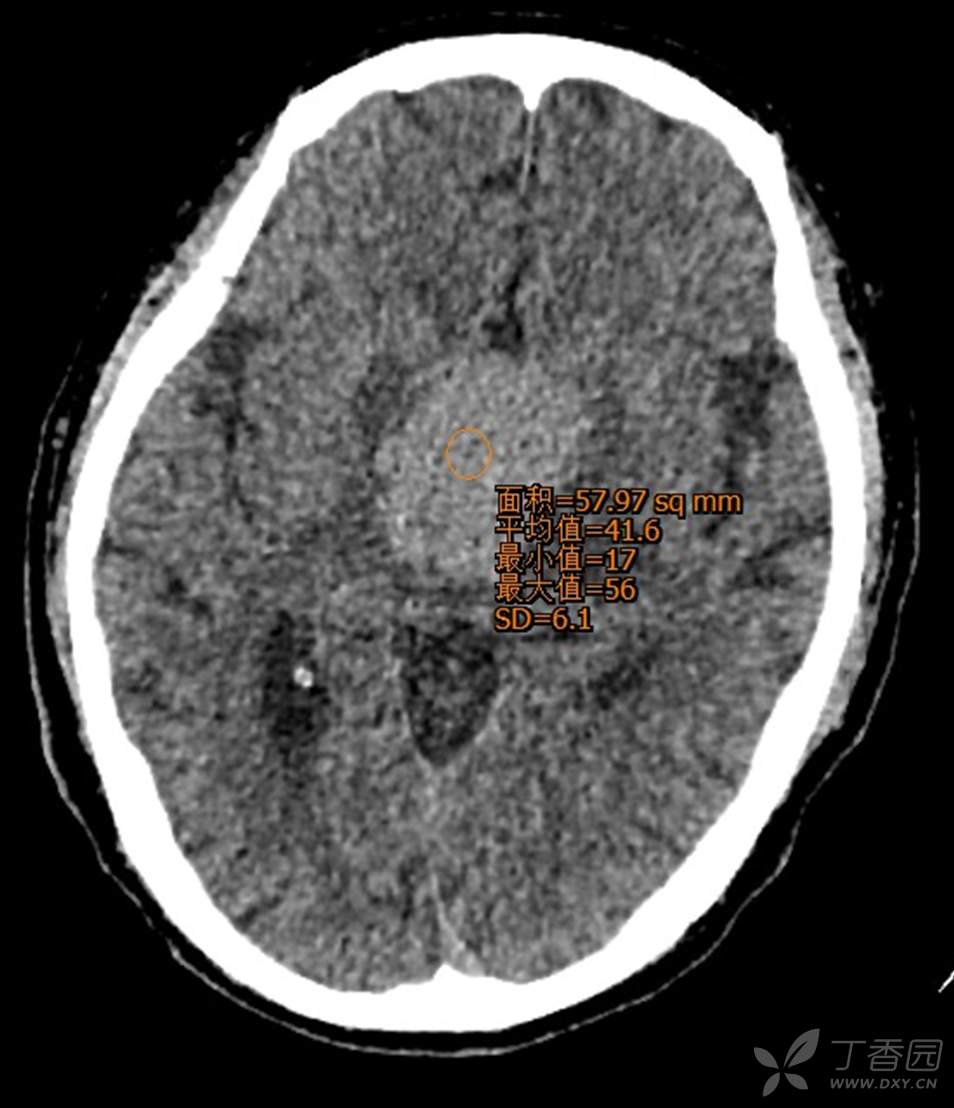

男,44岁,记忆力下降、乏力5月余,多尿3月余,CTMR全,疑难病例,能正确诊断吗?

图像不多,能诊断正确吗?有特征性吗?